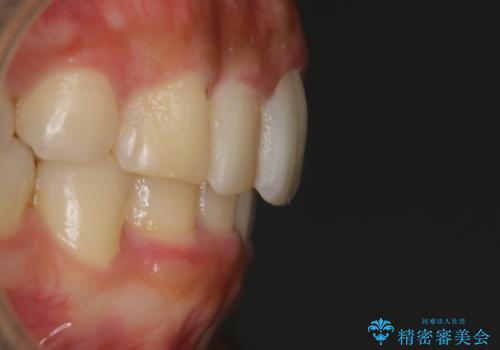

【非抜歯】インビザラインでガタつきと口元を改善!非抜歯でも印象が変わる矯正治療

- 歯のガタつきと口元の突出感を主訴に来院されました。

装置の希望がインビザラインだったため、非抜歯でインビザラインの特徴を最大限に生かして行う矯正治療を選択しました。

顔貌写真でも明らかに口の閉じやすさやEラインが改善している様子が分かります。